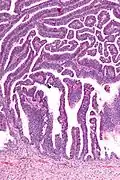

| Micrograph of a villoglandular adenocarcinoma the cervix. H&E stain. | |

The name of the lesion describes it microscopic appearance. It has nipple-like structures with fibrovascular cores (papillae) that are long in relation to their width (villus-like), which are covered with a glandular pseudostratified columnar epithelium.

Intermediate magnification -